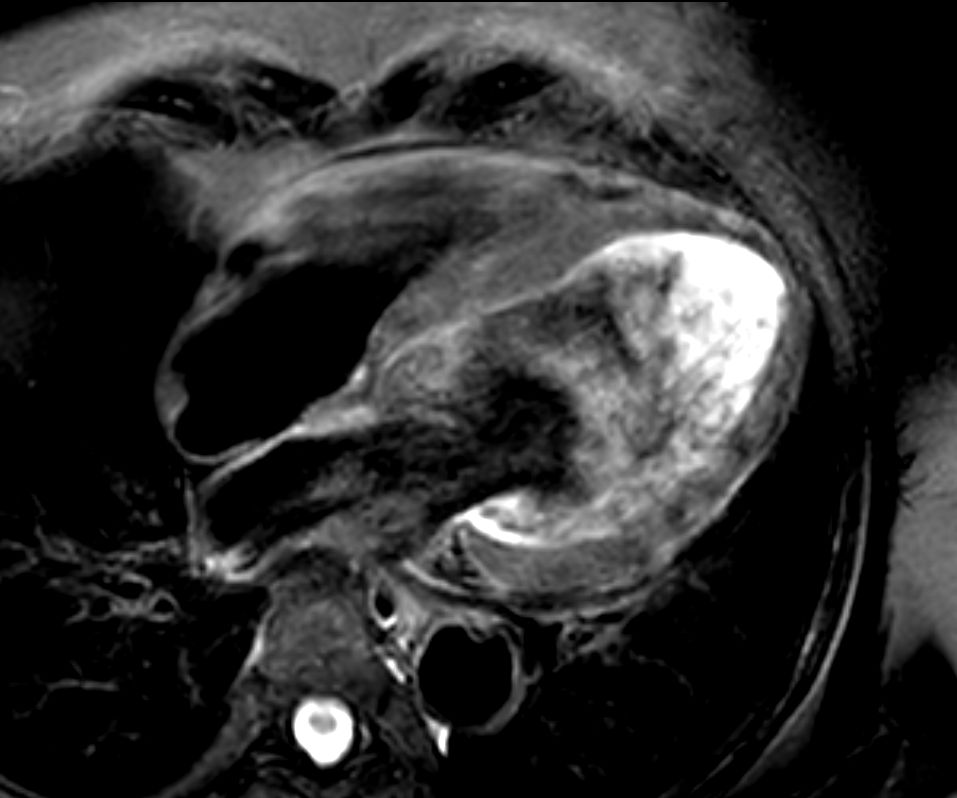

4 chamber view 3D PSIR

4 chamber view cine

4 chamber view T2w Black Blood